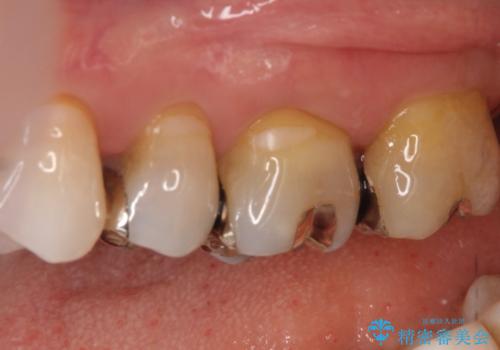

【メタルフリー】セラミックインレーによる治療

- 昔入れた銀歯のやりかえを主訴に来院されました。

セラミックインレーにて修復を行いました。

歯の強度を高めるためセラミッククラウンの提案もさせていただきましたが、患者様の希望でセラミックインレーにて修復を行なっております。